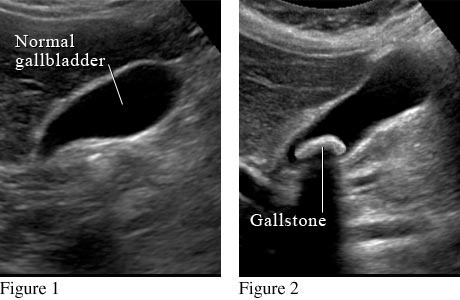

Abdominal Ultrasound Showing the Gallbladder

Figure 1 shows a normal gallbladder on ultrasound. Figure 2 shows a large gallstone in the gallbladder.